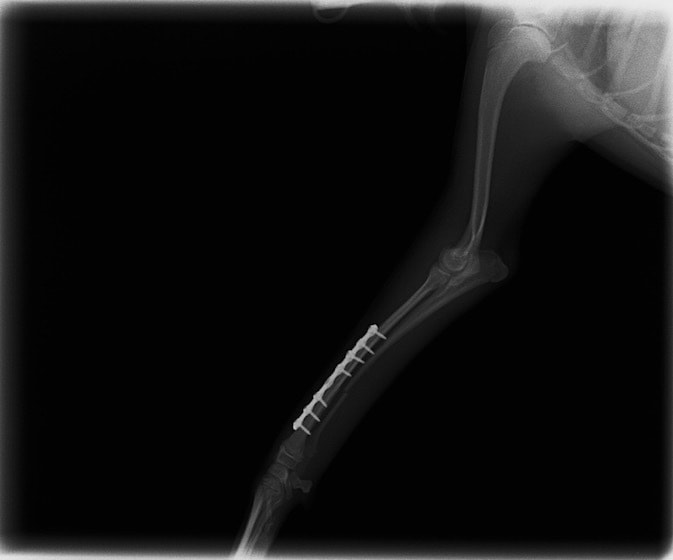

他院にて左大腿骨遠位の成長板骨折(salter-harrisⅠ型)が認められており、治療相談を目的として来院。当院にて、キルシュナーワイヤーを用いたピンニングにより骨折部位の整復を行いました。術後の経過は良好で、現在も経過観察中です。

術後レントゲン

Arthrex社のターゲティングデバイスを用いてピンニングの位置を調整することで、確実な固定を行っています。当院ではこの手術器具以外にも、人の手術にも使用される様々な器具を導入し、手術精度を高め、また医療メーカーと新しい器具の開発、試作にも取り組んでおります。